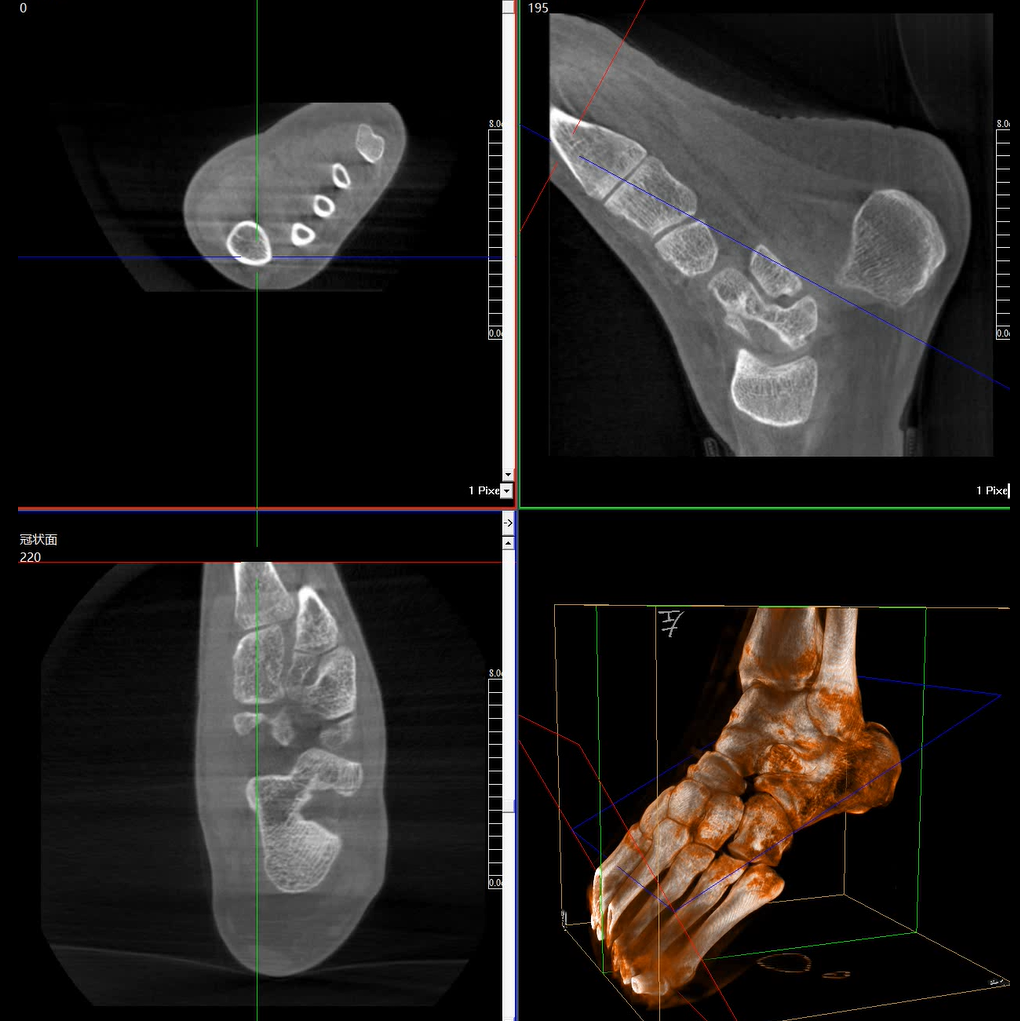

術(shù)中三維成像和橫斷面圖像提供多角度的手術(shù)診斷信息,輔助醫(yī)生進(jìn)行術(shù)中評估判斷,諸如骨折復(fù)位情況和內(nèi)植入螺釘?shù)某叽绾臀恢?,輔助手術(shù)更好地完成。

在C臂掃描過程中,始終保持拍攝主體處于射線束的中心,避免了序列圖像采集過程中的橫縱方向運(yùn)動(dòng),減少相對運(yùn)動(dòng)造成的運(yùn)動(dòng)偽影。

平板垂直升降運(yùn)動(dòng) 便于術(shù)中微調(diào)平板與拍攝主體的距離,更加貼近病灶體,成像范圍更大,圖像更清晰。